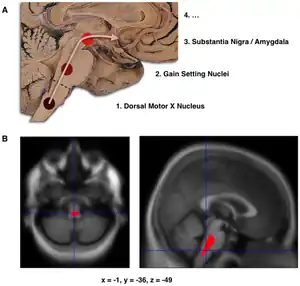

The main pathological characteristics of PD are cell death in the brain's basal ganglia (affecting up to 70% of the dopamine-secreting neurons in the substantia nigra pars compacta by the end of life).[54] In Parkinson's disease, alpha-synuclein becomes misfolded and clump together with other alpha-synuclein. Cells are unable to remove these clumps, and the alpha-synuclein becomes cytotoxic, damaging the cells.[74][75] These clumps can be seen in neurons under a microscope and are called Lewy bodies. Loss of neurons is accompanied by the death of astrocytes (star-shaped glial cells) and an increase in the number of microglia (another type of glial cell) in the substantia nigra.[76] Severity of progression of the parts of the brain affected by PD can be measured with Braak staging. According to this staging, PD starts in the medulla and the olfactory bulb before moving to the substantia nigra pars compacta and the rest of the midbrain/basal forebrain. Movement symptom onset is associated when the disease begins to affect the substantia nigra pars compacta.[77]

- Schematic initial progression of Lewy body deposits in the first stages of PD, as proposed by Braak and colleagues

- Localization of the area of significant brain volume reduction in initial PD compared with a group of participants without PD[78]